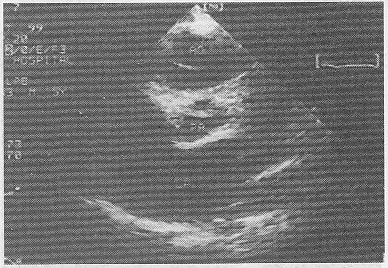

5.患者,男,30岁,常感心悸、气促,超声检查如图所示,该病例最可能的诊断是

正确答案:B 解题思路:室间隔与左室后壁非对称性肥厚。